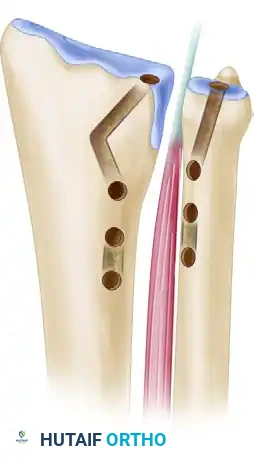

5. Preparation of the Ulnar Tunnel

- The ulnar tunnel must be directed obliquely from the fovea (the true isometric center of rotation) to the ulnar neck.

- Expose the fovea at the base of the ulnar styloid by flexing the wrist and retracting the remaining TFCC remnants distally.

- Insert a guidewire precisely at the fovea. Direct it to exit the ulnar neck medially, just palmar to the ECU sheath.

- Retrograde Reaming Technique: To avoid fracturing the delicate ulnar neck and to prevent injury to the carpus, place the 2- or 3-mm cannulated drill over the guidewire from the medial ulnar neck cortex. Ream from the superficial ulnar neck in a retrograde direction toward the fovea.

- Carefully enlarge the ulnar tunnel with noncannulated drill bits. The foveal opening must be large enough to accommodate the passage of both limbs of the tendon graft simultaneously.

While the Adams-Berger technique is the gold standard for anatomical reconstruction utilizing a single foveal tunnel, alternative methods exist for specific anatomical variants or revision scenarios.

The Scheker Technique is a notable alternative that utilizes a double-tunnel configuration. In this method, two distinct tunnels are created in both the distal radius and the distal ulna. This allows for a broader footprint of graft fixation, theoretically mimicking the broad origin and insertion of the native radioulnar ligaments. However, it requires a larger volume of bone and carries a higher risk of iatrogenic fracture during tunnel preparation.